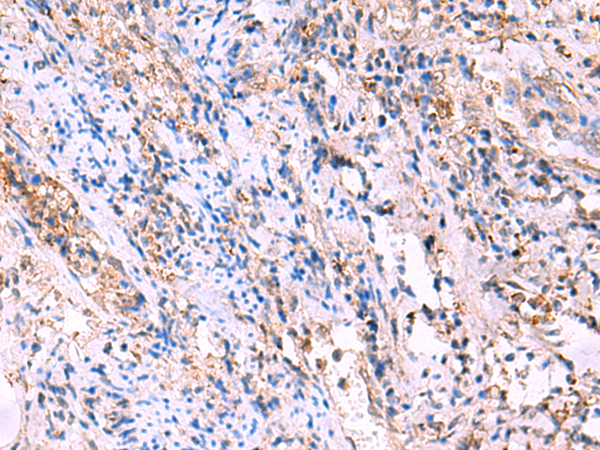

IHC positive control:

Human tonsil and Human cervical cancer